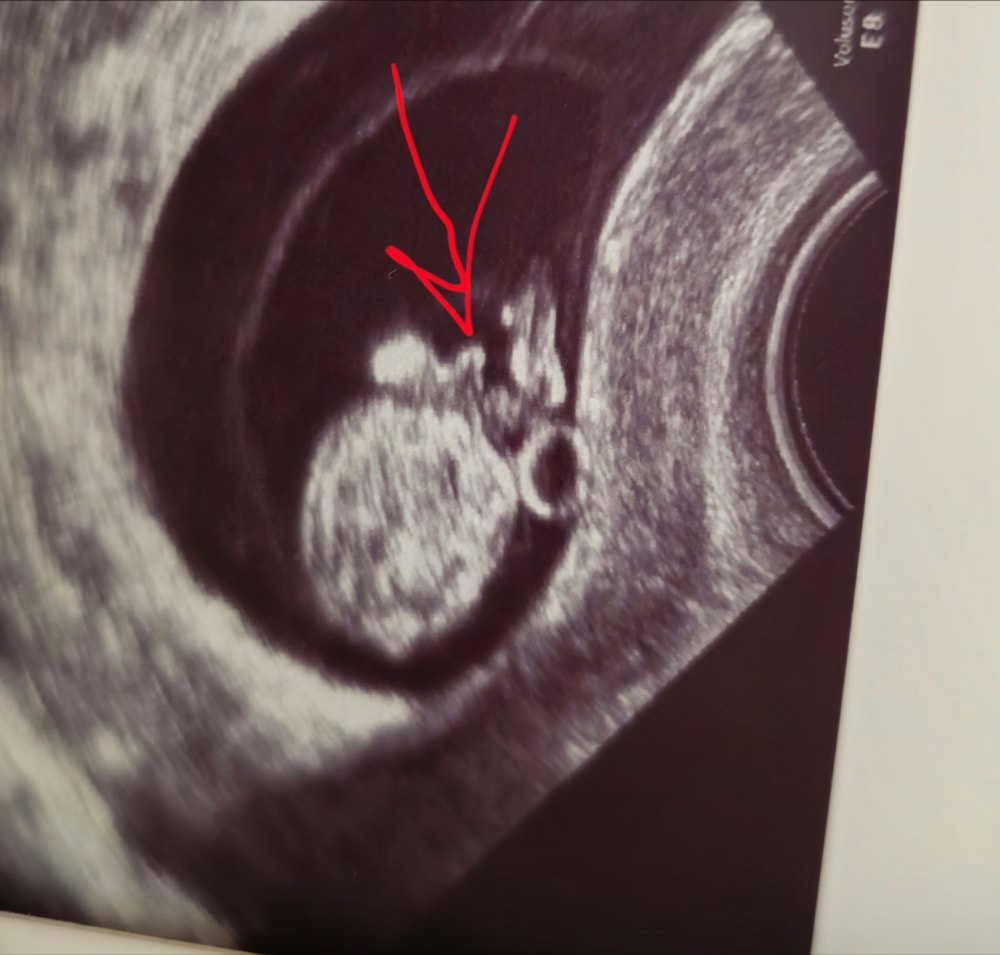

У кого на ранних сроках по узи определяли пол(1 триместр)? Подтвердился ли потом?Сегодня на узи рассматривали малыша,а он развинул ноги и там вывалились все пречандалы,я в шоке была.

У кого на ранних сроках по узи определяли пол(1 триместр)? Подтвердился ли потом?Сегодня на узи рассматривали малыша,а он развинул ноги и там вывалились все пречандалы,я в шоке была.